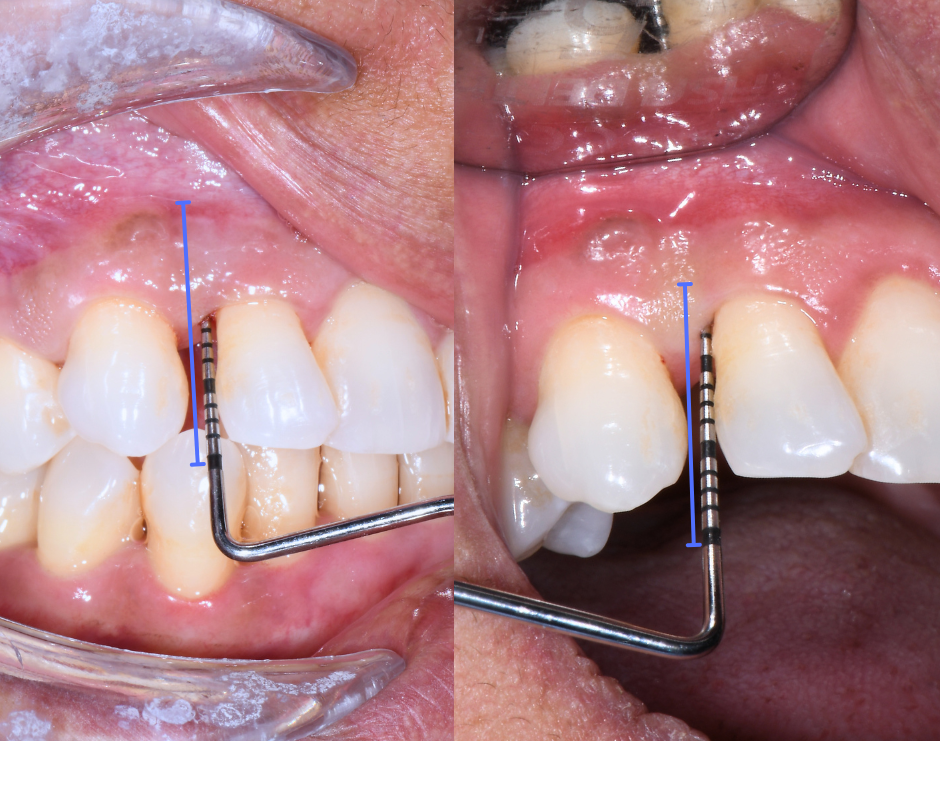

Le Tasche Gengivali

Questo è un segnale che spesso comunichiamo noi dentisti durante le visite. Usiamo uno strumento chiamato sonda parodontale - praticamente un piccolo righello metallico - che ci permette di misurare la profondità dello spazio tra gengiva e dente.

Se la sonda scende in profondità (oltre i 3-4mm), significa che lì sotto l'osso si è riassorbito. In quella zona si accumulano cibo e batteri che continuano a distruggere i tessuti circostanti.